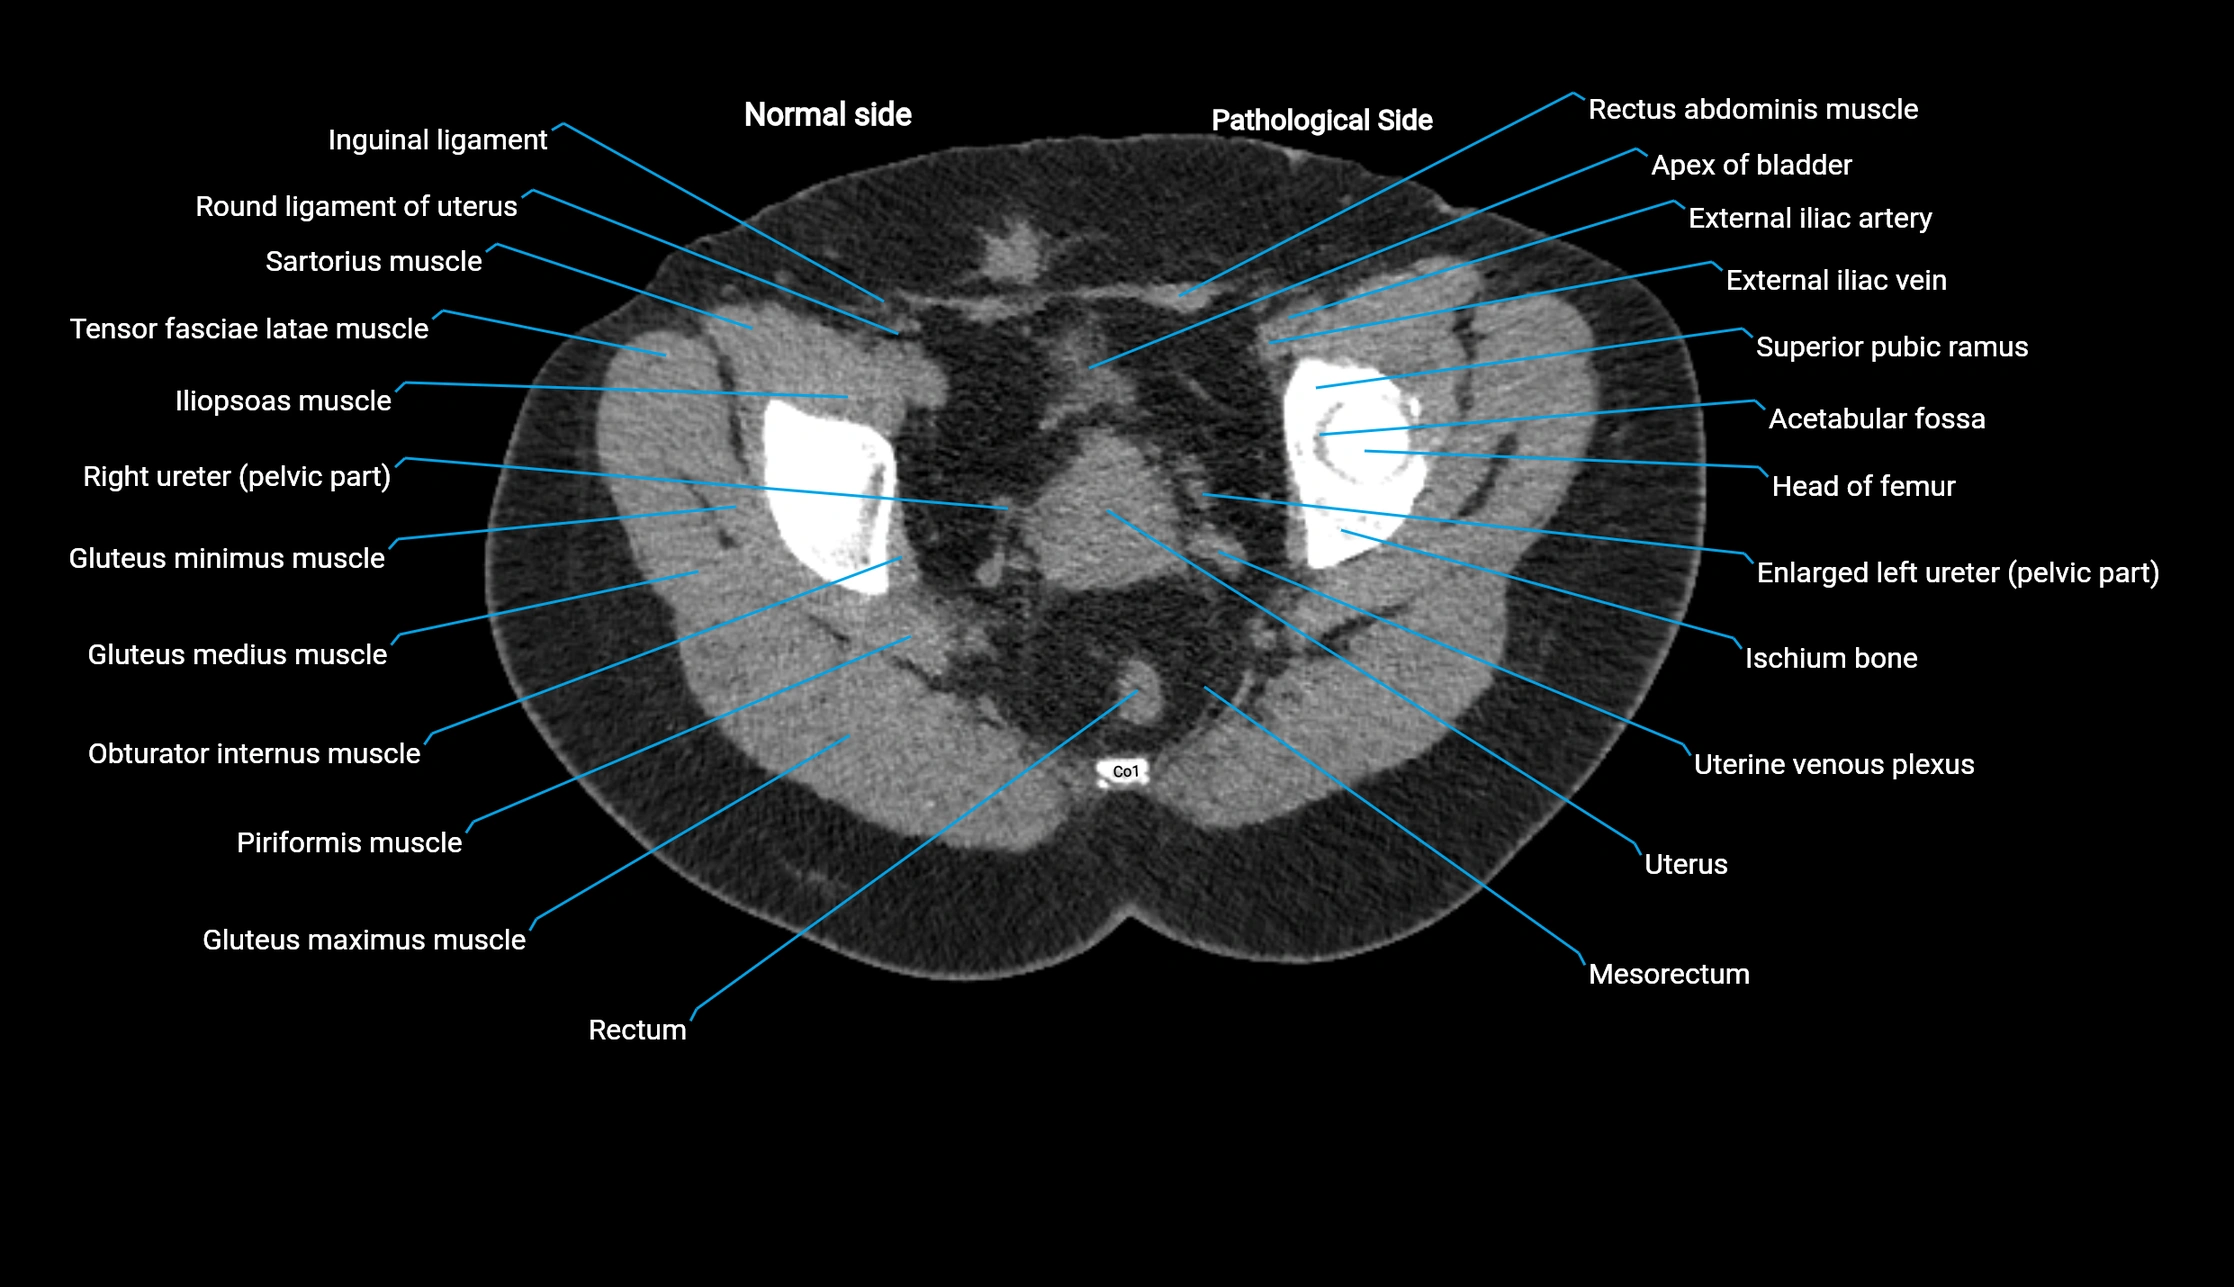

CT image

image